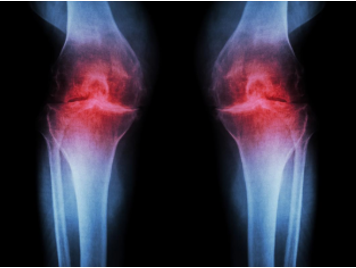

Biomarker and Antibody Development for Osteoarthritis Osteoarthritis is the most common form of arthritis affecting about 3.3% of the population. It is a type of joint disease that results from the breakdown of joint cartilage and underlying bone. Among those over 60 years old, about 10% of males and 18% of females are affected. It is the cause of about 2% of years lived with disability. It becomes more common in both sexes as people become older. Treatment includes exercise, efforts to decrease joint stress, support groups, and pain medications. Efforts to decrease joint stress include resting and the use of a cane. Weight loss may help those who are overweight. Pain medications may include paracetamol (acetaminophen) as well as NSAIDs such as naproxen or ibuprofen. Long-term opioid use is generally discouraged due to lack of information on benefits as well as risks of addiction and other side effects. If pain interferes with normal life despite other treatments, joint replacement surgery may help.

Osteoarthritis is a slow-developing disease that is hard to diagnose until it starts to cause painful or debilitating symptoms. Osteoarthritis is often diagnosed after an accident or incident that causes a fracture requiring an X-ray. Radiography, however, shows limitations such as technical issues, precision, and sensitivity. In addition to X-rays, doctors may also use an MRI scan. This imaging test uses radio waves and a magnetic field to create images of bone and soft tissue. However, the use of MRI is limited by cost, availability, and the absence of a validated international score.